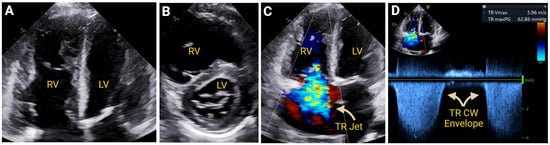

7.2.1. Pulmonary Hypertension